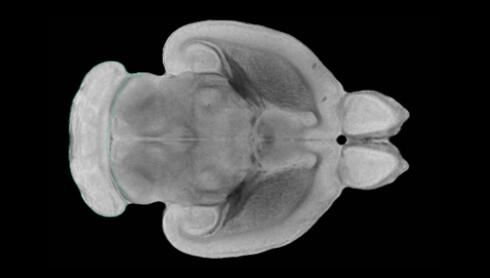

隨著機體年齡增加,肌肉和關節(jié)都會變得僵硬,這就會使得日?;顒幼兊酶永щy,本文研究表明,我們的大腦也是如此,與年齡相關的大腦僵硬對大腦干細胞的功能或許有著重要影響。文章中,研究人員對年輕和老化大鼠的大腦進行研究闡明了年齡相關大腦僵硬對少突膠質(zhì)前體細胞(OPCs,oligodendrocyte progenitor cells)功能的影響。OPCs是一類對維持正常大腦功能非常重要的大腦干細胞,其對于髓磷脂的再生也非常重要,髓磷脂是神經(jīng)組織周圍的脂肪鞘,在多發(fā)性硬化癥中髓磷脂的再生常常會被損傷,機體老化對這些細胞的影響常常會誘發(fā)多發(fā)性硬化癥的發(fā)生,這些細胞的功能在老化的健康人群中同樣會下降。

為了確定老化OPCs的功能缺失是否可以被逆轉(zhuǎn),研究人員將來自老化大鼠機體的老化OPCs轉(zhuǎn)移到了年輕大鼠柔軟的海綿狀大腦組織中去,值得注意的是,這些老化的大腦細胞能夠重新恢復活力,其行為非常像年輕更加強壯的細胞。這項研究中,研究人員在實驗室中開發(fā)出了具有可變僵硬程度的新型材料,并在受控環(huán)境下研究這些材料的生長及其對大鼠大腦干細胞的影響,這些材料能被工程化改造具有和年齡或老化大腦相似的柔軟程度。

為了深入理解大腦組織柔軟和僵硬影響細胞行為的分子機制,研究人員對細胞表面一種名為Piezo1的蛋白質(zhì)進行了分析,該蛋白質(zhì)能“告知”細胞其周圍的環(huán)境為柔軟或僵硬。研究者Kevin Chalut說道,我們發(fā)現(xiàn),當在僵硬材料上促進年輕具有功能性的大鼠干細胞時,這些細胞就會表現(xiàn)出功能異常,并失去其再生的能力,實際上其行為與老化細胞相似。當將老化的大腦細胞在柔軟材料上生長時,其功能就會表現(xiàn)得像年輕細胞一樣,換句話說,其能夠重新恢復年輕的活力。